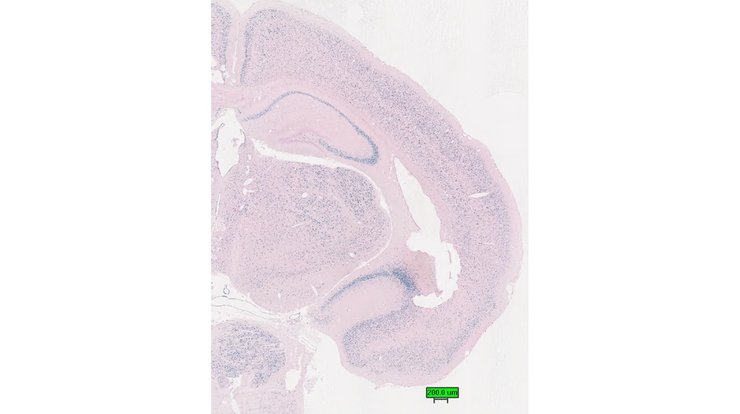

Specimen UC Davis_1878619: postnatal adult; Apbb2tm1.1(KOMP)Vlcg/Apbb2+ (more )

Structure Level Pattern Image Note

TS28: cerebellum Present UC Davis_1878619

Specimen UC Davis_1878662: postnatal adult; Apbb2tm1.1(KOMP)Vlcg/Apbb2+ (more )

TS28: cerebellum Present UC Davis_1878662